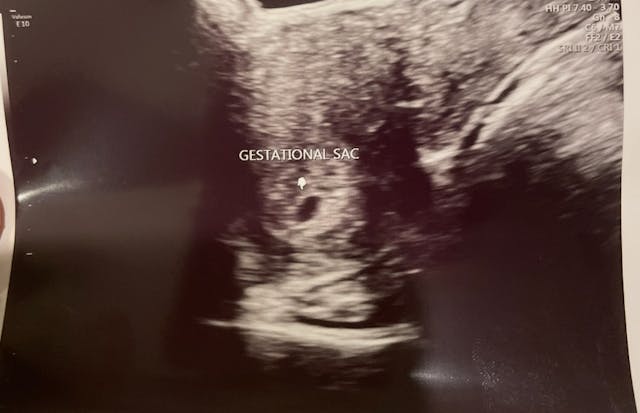

I’ve only ever seen my babies on ultrasound after they had already died. Not their heartbeats flickering, not their tiny movements — just the stillness of death where there should have been life.

That image is burned in me. The devastation of it cannot be explained. You go in hoping, praying for good news, for a miracle, and instead you’re met with silence.